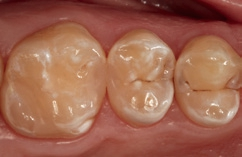

Fall 8 Multiple Läsionen an Zähnen 26 und 25

Bei dem 37-jährigen Patienten imponierte eine Approximalraumkaries mesial an Zahn 26 und distal an Zahn 25. Zudem waren okklusal und okklusal-palatinal (getrennt durch den Transversalgrad) zwei kleinere, randundichte ältere Amalgamfüllungen vorhanden, die ausgetauscht werden sollten. Der Patient hatte zunächst die Empfehlung einer Teilkronenversorgung erhalten; aufgrund der Situation nach der Exkavation und der noch sehr umfangreich vorhandenen Restzahnhartsubstanz erschien eine direkte, minimalinvasive Versorgung mit Komposit angebrachter. Die Abbildung 35 zeigt die bereits präparierten und mit Teilmatrizen (Contact Matrix Ultra thin flex, Danville, Spannring: Palodent V3, Dentsply Sirona) versehenen Kavitäten, die Abbildung 36 die Situation nach der adhäsiven Versiegelung mit einem klassischen Mehrflaschenadhäsiv (Optibond FL, Kerr). Auch hier war aufgrund der guten Compliance und der suffizienten zervikalen Abdichtung über die Matrize ein Arbeiten unter relativer Trockenlegung sehr gut möglich. Die Abbildung 37 zeigt das Behandlungsergebnis bei einem Kontrolltermin nach zwei Wochen. Die beiden approximalen Kavitäten wurden ausschließlich mit SDR flow+ in der Farbe A2 versorgt, die okklusal-palatinale und die separate okklusale Kavität hingegen mit einem konventionellem Komposit (ceram.x universal, Dentsply Sirona). Die Wahl fiel hier auf das pastöse Material, da mit diesem die Ausmodellation der Fissur einfacher gestaltet werden konnte. Die in der Abbildung erkennbare, approximal nicht kavitierte Initialläsion distal an Zahn 24 wird durch regelmäßige Intensivfluoridierung über eine Remineralisation therapiert und halbjährig gemonitort.